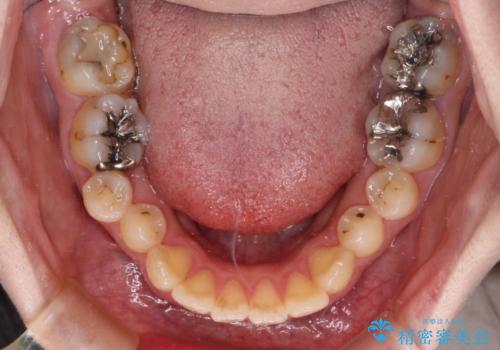

- 捻れた前歯が飛び出しており、口が閉じにくいとのことで来院された患者様です。

出っ歯というわけではないものの、前歯の捻転により口唇が押し出されている状態でした。

親知らずを抜去し、歯列全体を後方に移動させつつ、IPR(歯と歯の間を削る)でスペースを獲得し、インビザラインを用いて叢生を解消しながら前歯の突出を改善することとしました。

インビザラインは、患者様の協力無しには成立しない治療ですが、しっかりと装着時間を遵守してくださり、1年弱で治療を終えることができました。